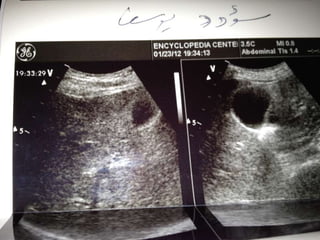

A 43-year-old Arabic woman presented with dyspepsia, vomiting, and weight loss for one month. On examination, she had evident weight loss but no other abnormalities. She was diagnosed with pancreatic head cancer and sent to surgery for bypass surgery and a histological diagnosis. This case demonstrates that dyspepsia with alarm features like weight loss and anemia in those over 45 should prompt consideration of pancreatobiliary causes and appropriate imaging if upper GI pathology is not found.